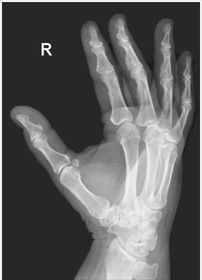

| PA Hand | distal phalynxes are bent flatten hand to true PA *should be equal concavity on all digits* |

| PA Hand | obliqued - fingers are not equally concave on both sides distal metacarpals are overlapped |

| Oblique Hand | Overly obliqued - metacarpals superimposed joint spaces closed - fingers bent |

| Oblique Hand | MCP joints superimposed - fingers too close together *underexposed |

| Oblique Hand | joint spaces closed hand overly obliqued MCP joints superimposed |

| PA Hand | ANATOMY: entire hand including 1'' of distal radius and ulna CRITERIA: equal concavity on either side of digits digits separated with no superimposition open joint spaces POSITIONING: CR perpendicular @ 3rd MCP joint |

| Oblique Hand | ANATOMY: entire hand including 1'' of distal radius and ulna CRITERIA: digits more concave to one side minimal overlap of 3rd-5th metacarpal shafts separation of the 2nd and 3rd metacarpals POSITIONING: CR perpendicular @ 3rd MCP joint |